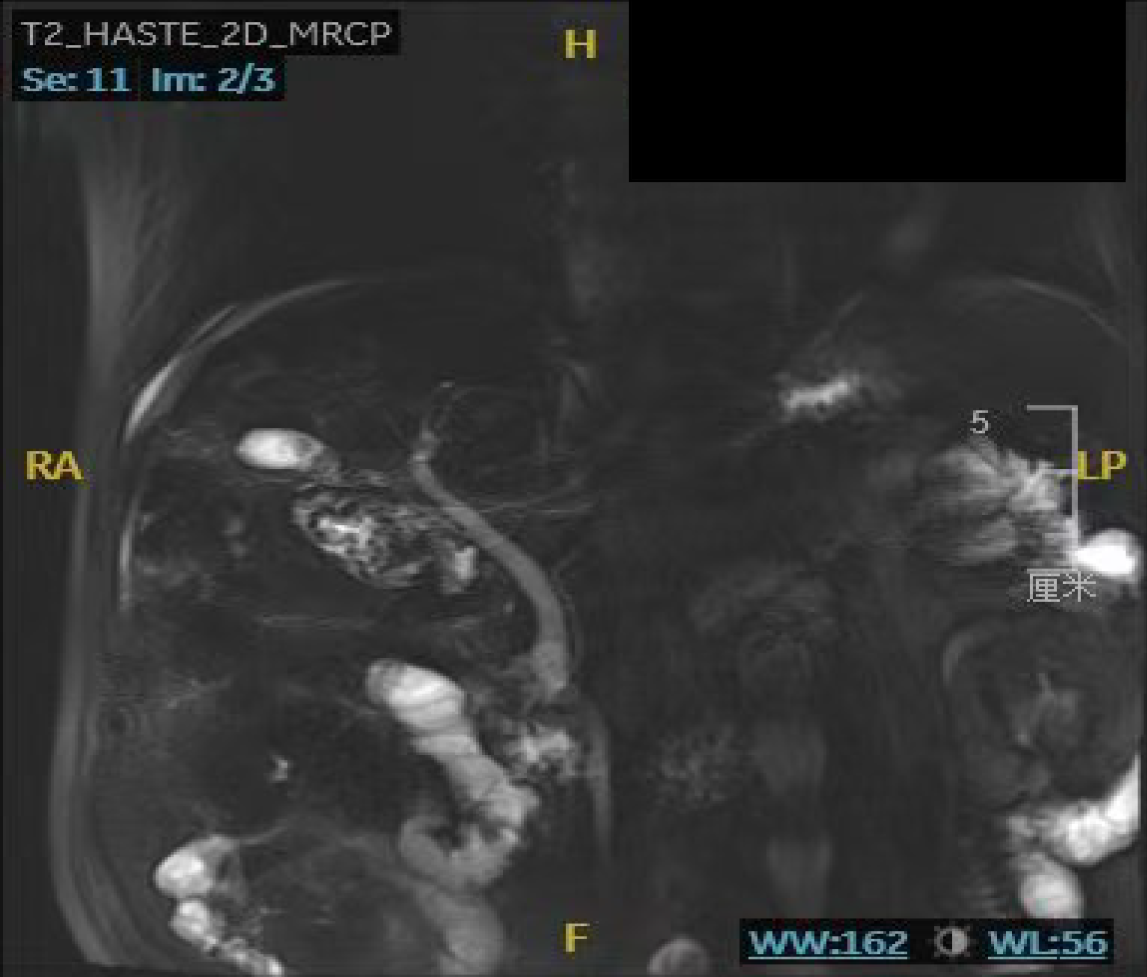

Figure 3 Upper abdominal magnetic resonance imaging with magnetic resonance cholangiopancreatography performed on September 18, 2024.

A: Common bile duct stone (orange arrow); B: Gallbladder stones (blue arrow), poor visualization of the bile duct at the hepatic portal region (green arrow).